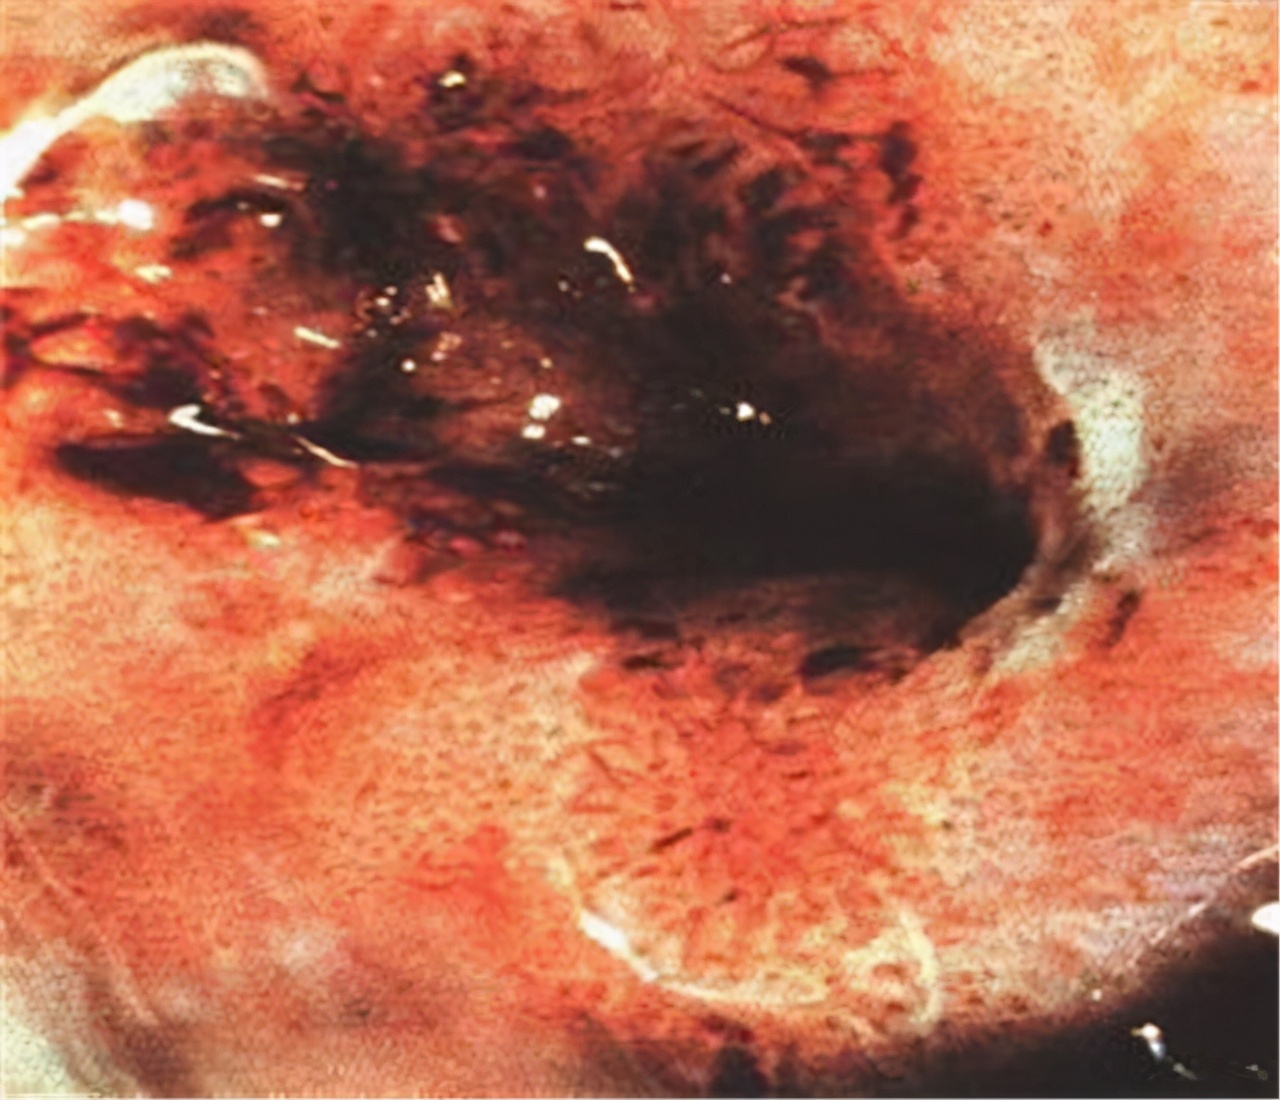

● 晚期:宫颈癌

患者50岁,宫颈癌晚期,肉眼可见宫颈口有坏死出血,宫颈被增生组织覆盖,一般发展到宫颈癌晚期就需要采用 手术治疗配合化疗 ,以减少病灶带来的疼痛感。大多数宫颈癌晚期患者的存活时间 不超过5年 。该名患者长期精神压力过大,工作劳累,有研究表明, 过度劳累 也是诱发宫颈癌发作的因素之一,因此也希望大家在平时的工作生活中, 保持乐观的情绪 ,学会调节自己的情绪,做情绪的主人。